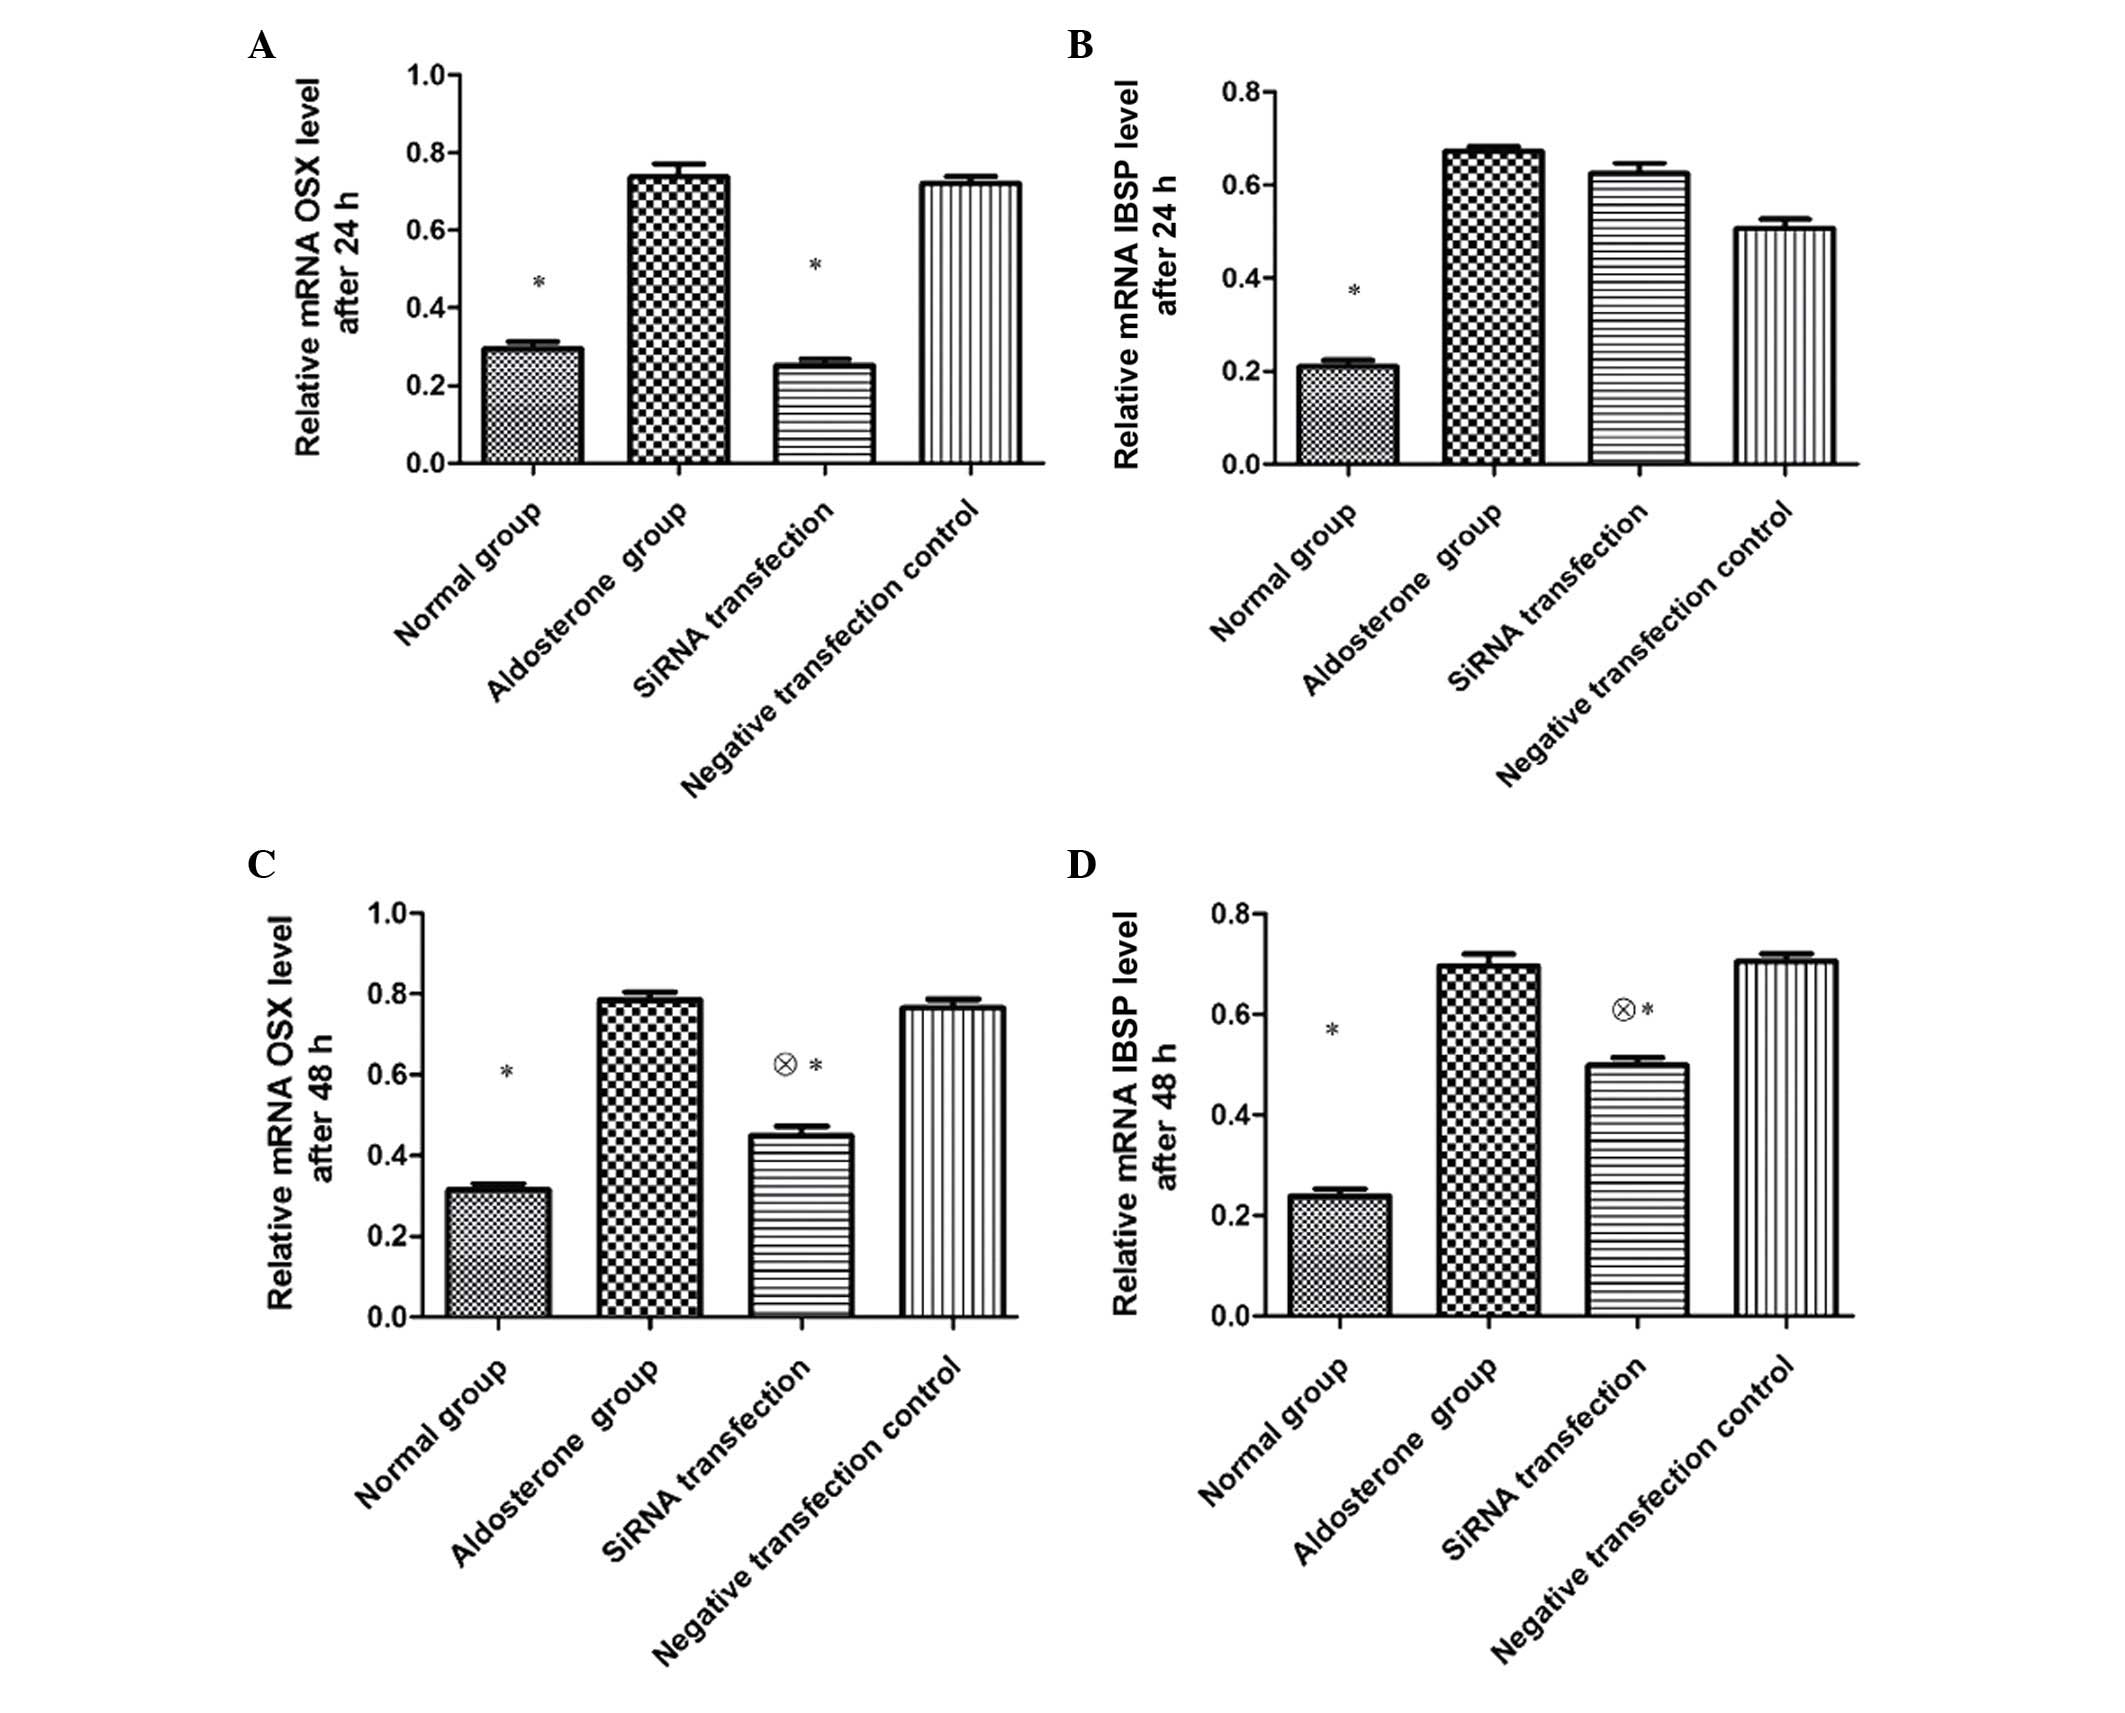

Following 24-h transfection, the expression of both

OSX and IBSP mRNA in VSMCs of the ALD group was significantly

higher than that of the normal group (P<0.01), and the

expression of OSX mRNA in the siRNA transfection group was

significantly lower than that of the ALD and negative transfection

control groups (P<0.01). No significant differences were

observed in IBSP mRNA expression between the three groups

(P>0.05). Subsequent to 48-h transfection, the expression of OSX

mRNA in the siRNA transfection group remained significantly lower

than that of the ALD and negative transfection control groups

(P<0.05), however was increased compared with the normal group

(P<0.01). The expression of IBSP mRNA in the siRNA transfection

group was significantly lower than that of the ALD and negative

transfection control groups (P<0.05), however was higher than

that of the normal group (P<0.01) (Fig. 3).